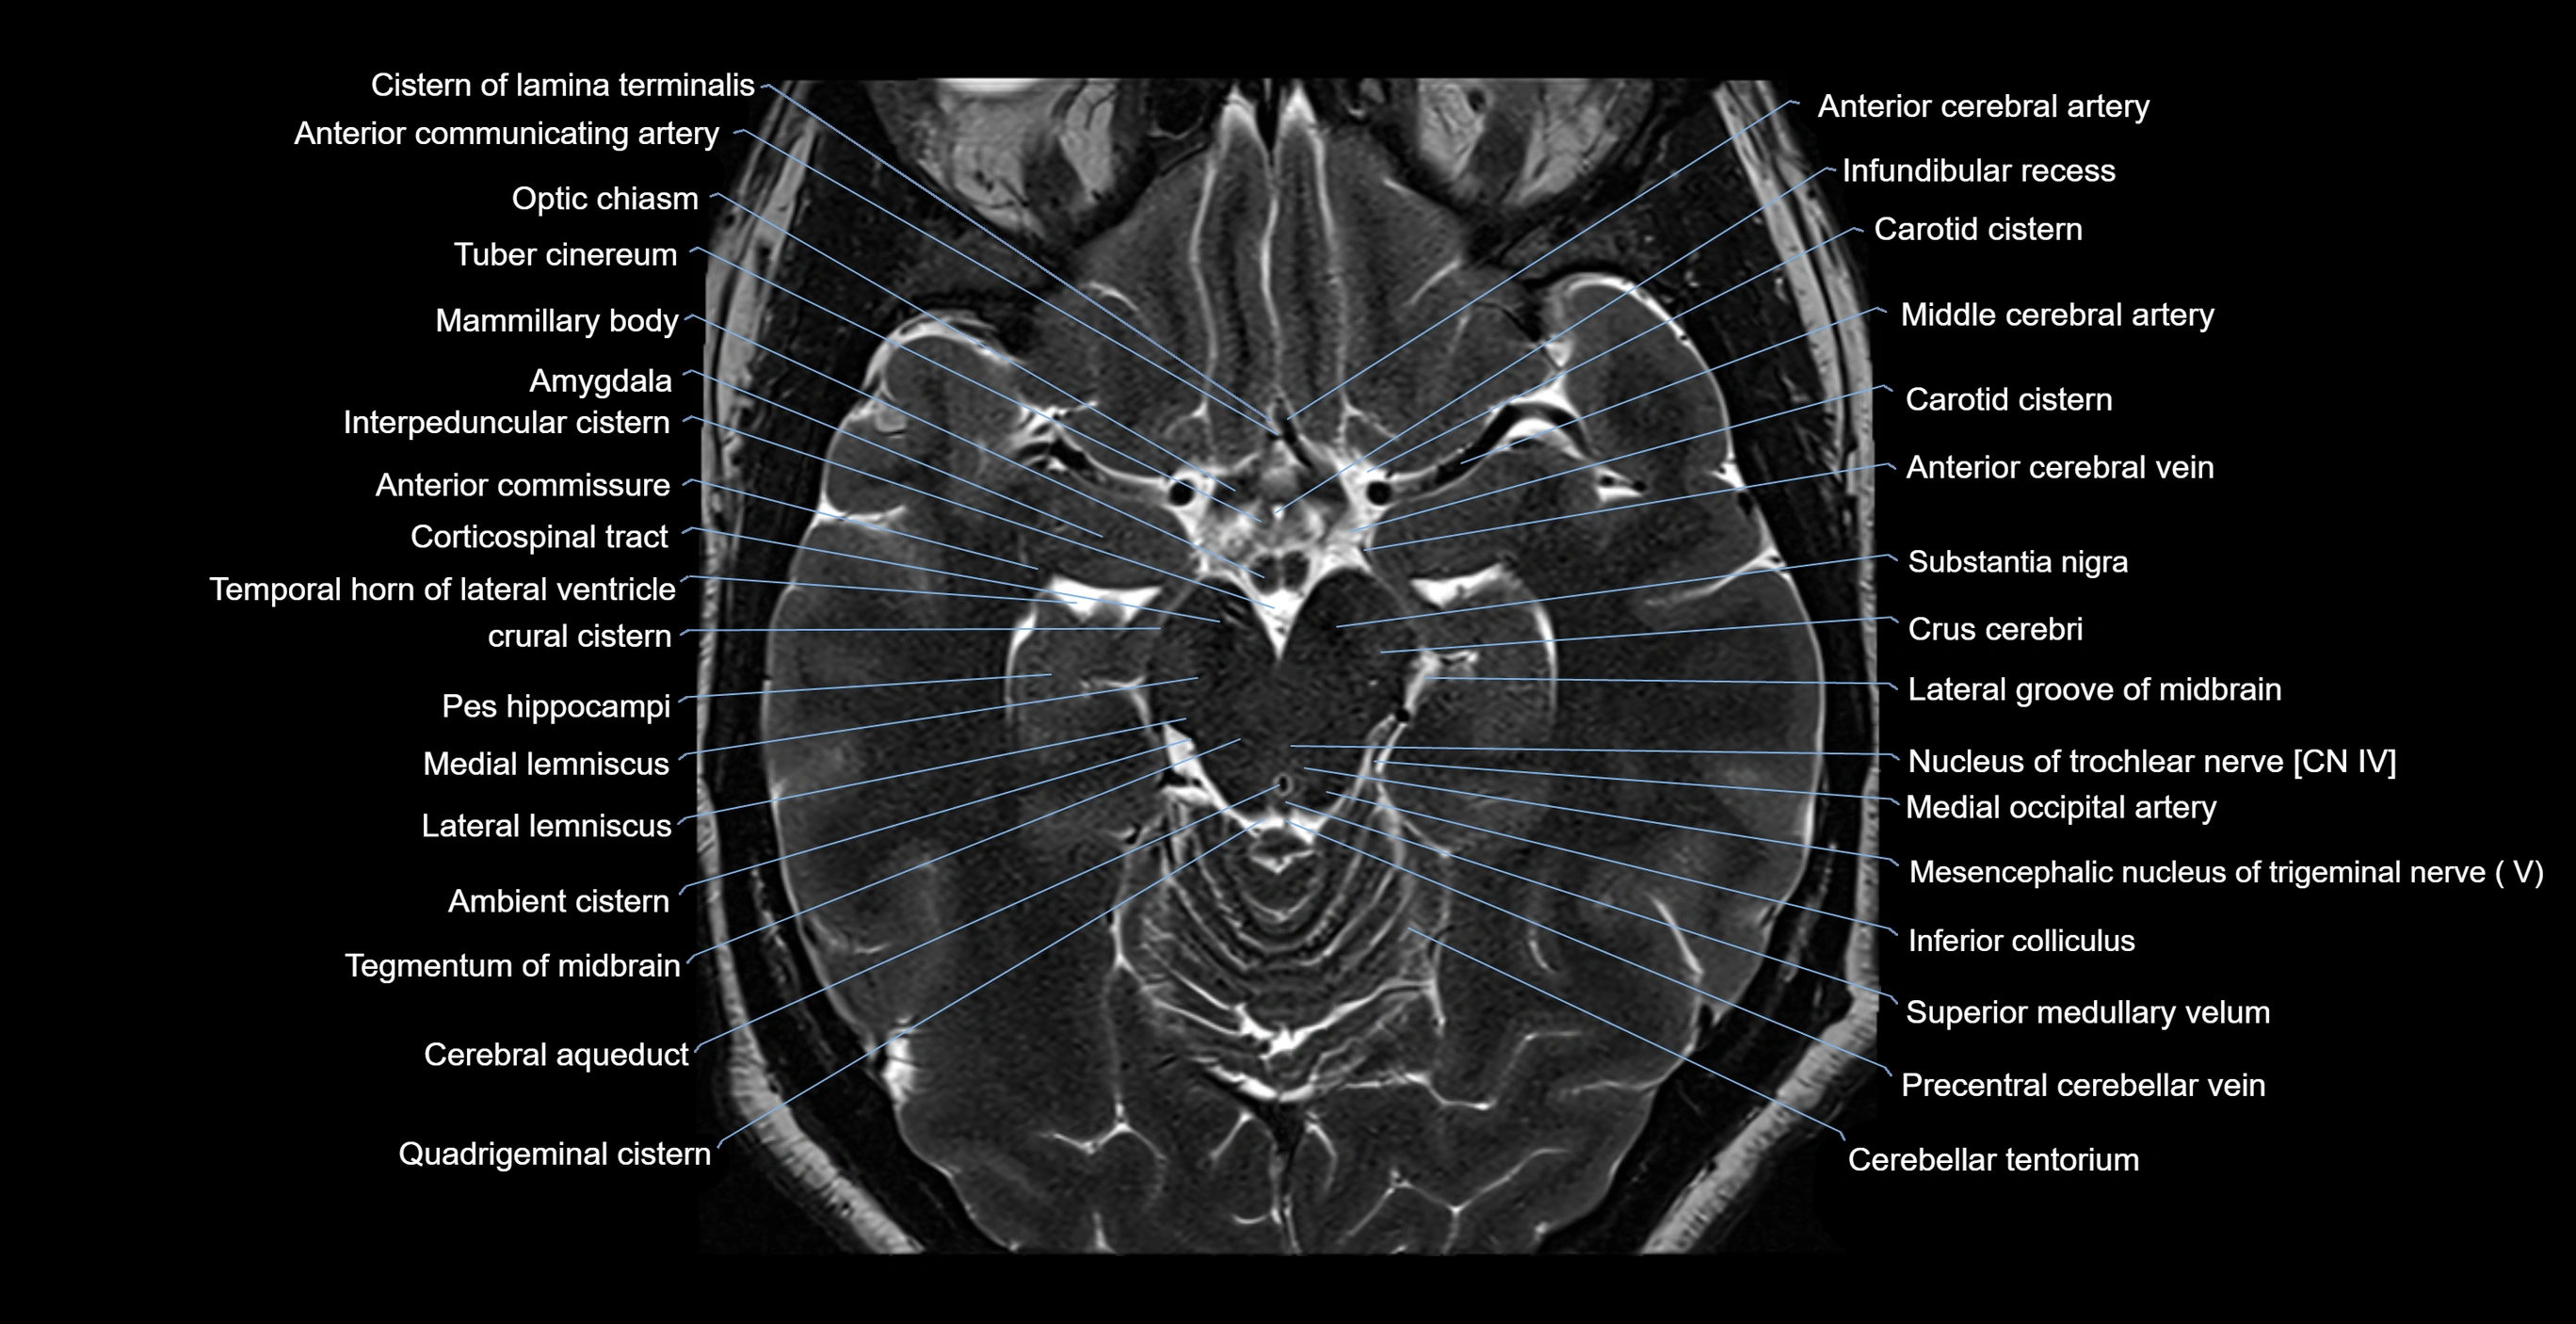

MRI images